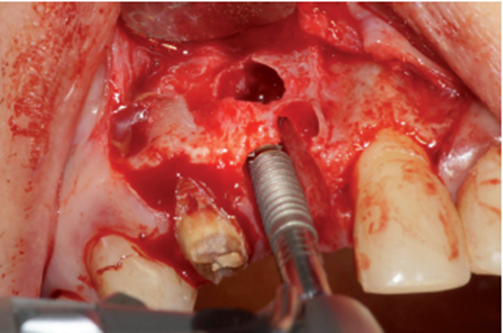

O procedimento cirúrgico foi iniciado através de uma anestesia infiltrativa com articaína 4%. Foram realizadas incisões relaxantes (Figura 4) para expor o leito cirúrgico e, consequentemente, a lesão periapical (Figura 5). Após o deslocamento do retalho, foi realizada a exodontia de forma atraumática (Figura 6) e na sequência, foi feita a curetagem do alvéolo removendo todo o tecido de granulação (Figura 7). Uma vez realizada a toalete do leito cirúrgico (Figuras 8 e 9), o implante Cone Morse Due Cone de 3.5 X 13 mm (Implacil De Bortoli) foi instalado seguindo o melhor posicionamento dentro do rebordo residual, conforme planejado (Figuras 10 e 11). Em sequência, foi realizada a instalação do Cover Screw (Figura 12) e o preenchimento do defeito ósseo com biomaterial (Bio-Oss 0,25), conforme figuras 13 e 14). O fechamento foi realizado com membrana de PTFE-d (Cytoplast TXT–200, Osteogenics – Lubbock TX, EUA), customizada para ser adaptada sobre o defeito ósseo, estendendo-se de 3 a 5 mm da margem do defeito ósseo e intencionalmente exposta (Figura 15). A sutura foi realizada com fio de PTFE (Cytoplast), como podemos observar na figura 16, e instalado um provisório adesivo na região (Figura 17).